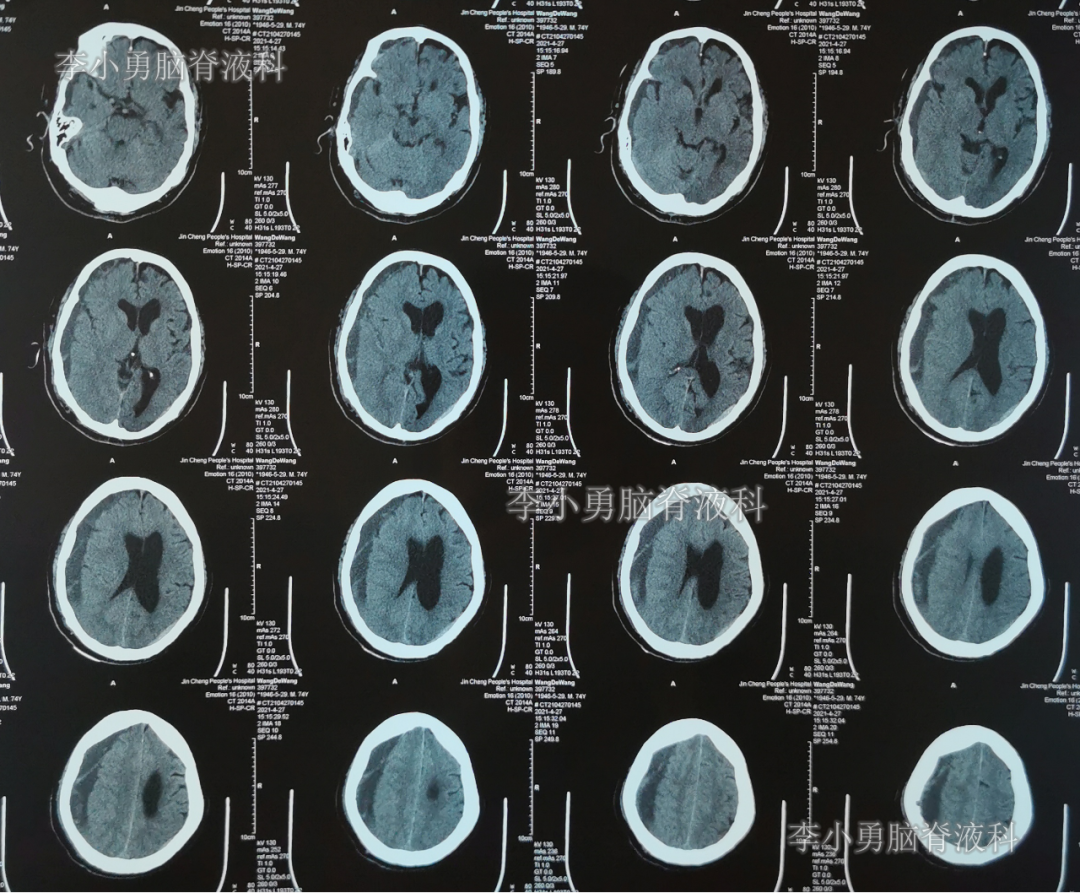

出院后再次转住入当地的第1家医院进行康复治疗,在该院康复治疗半年多的时间,不但没有持续好转,反而再次腰疼,走路不稳,且还出现了尿失禁的持续加重症状;治疗期间曾6次查头部影像(图-13、图-14、图-15、图-16、图-17)均示脑积水不断加重的趋势。

图-13:2021年5月22日头部核磁

图-14:2021年6月2日头部核磁

图-15:2021年7月24日头部核磁

图-16:2021年8月28日头部核磁

图-17:2021年9月28日头部CT